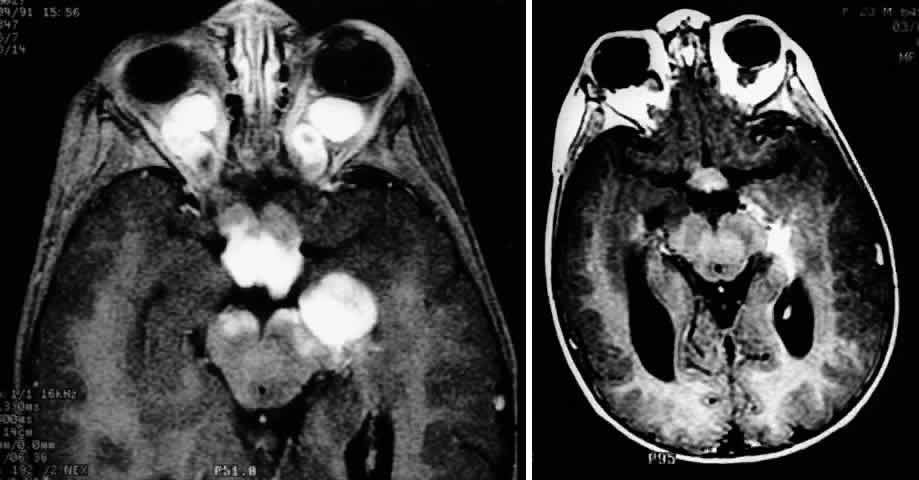

| Plain-film orbital X-ray may reveal concentric enlargement of the optic

foramen with preservation of a well-corticated margin due to a slow growth

of the tumor.4 A criterion for abnormality in one study that did not include any false-positives

in children is an optic foramen of 7 mm diameter, or 6.5 mm

and at least 1 mm larger than the contralateral foramen.67 Enlargement of the optic canal does not necessarily imply intracranial

extension of the glioma, because dural thickening and arachnoid hyperplasia

may cause such changes.68,69 In the series of Chutorian and colleagues, foramen enlargement was present

in 83% of patients with involvement of one optic nerve and in 67% of

those with chiasmal involvement.29 The pressure of the glioma on the anterior clinoid process and lateral

chiasmatic groove may produce a fossa with continuity of the optic canal, creating

a J-, pear-, or gourd-shaped sella turcica.70 Tumors that less commonly produce a similar flattening include trans-canalicular

extension of intraorbital neurofibromas, perioptic extension

of a craniopharyngioma, or pituitary adenoma.4 With the availability of computerized tomography (CT) and magnetic resonance imaging (MRI), invasive diagnostic techniques such as arteriography and pneumoencephalography should not be performed in the routine workup of presumed optic gliomas.71 CT scanning may demonstrate enlargement of the optic nerve or chiasm by a glioma (Fig. 3). Because optic gliomas typically appear isodense to normal brain,72 and because the degree of contrast enhancement ranges from imperceptible to moderate on CT imaging,73 the margins of the tumor may not be well delineated. Optic gliomas usually have a well-outlined fusiform shape, which may include kinking or buckling of the optic nerve. Chiasmal tumor appearance may range from a tubular thickening of both optic nerves and chiasm to massive, multilobular growths.74 Cystic spaces representing mucinous accumulation have been described. These cysts may enlarge and damage adjacent structures, requiring surgical intervention.74,75 Calcific change has also been documented in gliomas, but it is a rare radiologic finding.13 In following patients clinically, it is important to understand that radiologic progression of optic gliomas on CT scans may not correlate clinically with worsening visual function. Conversely, a decline or improvement in visual status may occur despite a lack of corresponding changes on neuroimaging.73,76 MRI has replaced CT scanning as the optimum test for imaging optic gliomas (Fig. 4 A and B). Optic gliomas have normal to slightly prolonged T1 relaxation times and appear isointense to slightly hypointense to normal brain on T1. Because many of these tumors have prolonged T2 relaxation times, images that are T2 weighted may be used to assess gross tumor margins and posterior extension.72 Optic nerve gliomas often demonstrate minimal enhancement after administration of contrast. To improve MR imaging of optic nerve lesions, a gadopentetate dimeglumine enhancement technique combined with fat suppression can be utilized. Unlike meningiomas, the thickened sheath from arachnoid hyperplasia associated with gliomas will not enhance.77 Although imaging should initially be performed in the axial plane to allow visualization of both the optic nerve and the posterior optic pathways, sagittal views are helpful in demonstrating chiasmal involvement; coronal views can be utilized to delineate intracanalicular tumor.78 MRI has several advantages over CT scanning. In addition to sparing children from exposure to ionizing radiation when multiple scans are required, MRI eliminates bony artifact and is superior in evaluating the intracanalicular, chiasmal, and postchiasmal extension of the tumor.78 Brown and associates79 reported 10 posteriorly located lesions by MRI, none of which were visualized by CT. Anterior pathway lesions were detected with equal sensitivity by both modalities. Unfortunately, microscopic spread of gliomas can go undetected by both CT and MRI. In addition to detecting bilateral optic nerve glioma, other MRI findings can suggest an association between an optic nerve glioma and NF-1. One imaging characteristic to watch for is double-intensity tubular thickening, which is seen as a high T2 signal surrounding the optic nerve. This radiologic finding has been termed a “pseudo-CSF” signal and can be misinterpreted as cerebrospinal fluid in a dilated subarachnoid space.80 The high T2 signal arises from perineural arachnoidal gliomatosis, a histopathologic pattern most commonly seen in NF-1-associated gliomas.60 Elongation of the nerve secondary to axial growth of the perineural tumor as well as downward kinking of the nerve in the midorbit are other features suggestive of NF-1-related gliomas.80 Neuroimaging studies have demonstrated that NF-1 patients may have more extensive glioma involvement of the visual pathway than patients who do not have NF-1.79,81 Despite this difference in visual pathway involvement, the same investigators81 noted a lower incidence of progressive neurologic deficits and visual symptoms in NF-1-related glioma patients compared with patients whose gliomas were unrelated to NF-1. MRI scanning of NF-1 patients may also demonstrate aqueductal stenosis, idiopathic macrocephaly, and unidentified T2-weighted signals in the basal ganglia, internal capsule, midbrain, cerebellum, and subcortical white matter.51,64,82 In the appropriate clinical setting, characteristic neuroimaging appearances consistent with intrinsic optic pathway enlargement can usually permit a diagnosis without a surgical biopsy.13,71 Hoyt and associates73,74 noted the following radiologic features on CT scanning that they considered diagnostic for optic chiasm gliomas:

Globular tumors in the suprasellar area that lack these features usually require craniotomy and biopsy confirmation. Lesions that may be difficult to distinguish from optic pathway gliomas include germinomas of the visual system and optic nerve choristoma because they both may appear intrinsic to the visual pathway.13 Tumors such as craniopharyngiomas and pituitary adenomas usually do not appear intrinsic to the visual pathway and may have features of sellar enlargement. Findings such as enhancement of the leptomeninges or peripheral enhancement of an enlarged chiasm are atypical of optic glioma and may indicate an inflammatory process masquerading as a glioma.83 Aneurysms in the suprasellar area may sometimes appear on neuroimaging to be intrinsic to the visual pathway. Better definition may be noted with magnetic resonance angiography.13 In contrast to orbital optic nerve gliomas, meningiomas enhance strongly with gadolinium and are less common in children. Meningiomas have the following features on axial CT scanning that are not typically shared by optic nerve gliomas: